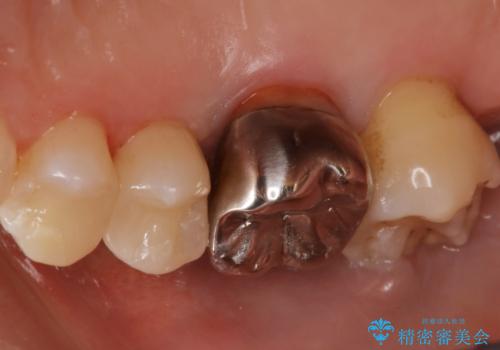

- 下の奥歯が黒いことが気になり来院された患者様です。

レントゲンなどから隣接面にも、う蝕があることが判明しました。

海外に引っ越す予定があり、見ため(審美性)強度ともに良い被せ物を希望されたため、セラミックインレーにて治療を行いました。

一部歯に保険治療で使用されている材料が劣化していたため、う蝕と一緒に取り除いて劣化の少ないセラミックに置き換わりました。